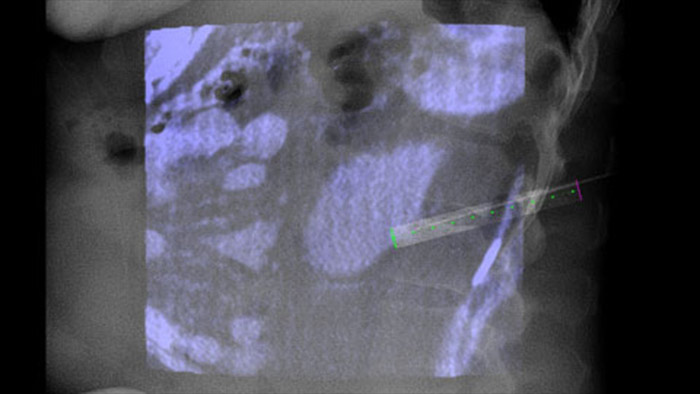

XperGuide Ablation* bietet umfassende Unterstützung bei der Behandlungsplanung und Echtzeit-Nadelnavigation. Die spezielle Parallaxenkorrektur ermöglicht die Planung von Nadelverläufen bei außermittigen Läsionen.1 Um eine möglichst gute Nadelposition für eine wirksame Ablation zu erreichen, zeigt dieses Tool den virtuellen Nadelverlauf an. Auch die Planung mehrerer Ablationsnadeln wird dadurch unterstützt. Außerdem werden Nadeleigenschaften wie Ablationszone/Isotherm angezeigt, damit die vollständige Tumorabdeckung vor der Ablation verifiziert werden kann.

XperGuide bietet eine besonders präzise Live-Bildführung für jede Nadel zur Zielposition. Hierfür wird das Durchleuchtungsbild mit den vorab geplanten Bewegungsverläufen überlagert.3